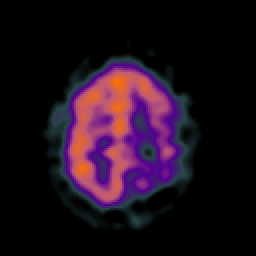

SPECT TC Study #5 -- Slice #41

[Home][Help][Clinical][Tour 1][Tour 2][Tour 3] Slice 41